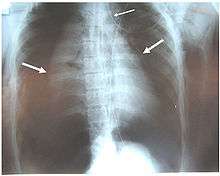

Pneumothoraces of both lungs (large arrows), pneumomediastinum (small arrow) and subcutaneous emphysema in a patient with complete disruption of the right bronchus. Air leak was continual despite suction.[1]

Signs and symptoms vary depending on what part of the tracheobronchial tree is injured and how severely it is damaged.[6] There are no direct signs of TBI, but certain signs suggest the injury and raise a clinician's suspicion that it has occurred.[16] Many of the signs and symptoms are also present in injuries with similar injury mechanisms such as pneumothorax.[17] Dyspnea and respiratory distress are found in 76–100% of people with TBI, and coughing up blood has been found in up to 25%.[14] However, isolated TBI does not usually cause profuse bleeding; if such bleeding is observed it is likely to be due to another injury such as a ruptured large blood vessel.[2] The patient may exhibit dysphonia or have diminished breath sounds, and rapid breathing is common.[3] Coughing may be present,[18] and stridor, an abnormal, high-pitched breath sound indicating obstruction of the upper airway can also occur.[19]

Damage to the airways can cause subcutaneous emphysema (air trapped in the subcutaneous tissue of the skin) in the abdomen, chest, neck, and head.[2] Subcutaneous emphysema, present in up to 85% of people with TBI,[14] is particularly indicative of the injury when it is only in the neck.[20] Air is trapped in the chest cavity outside the lungs (pneumothorax) in about 70% of TBI.[4][14] Especially strong evidence that TBI has occurred is failure of a pneumothorax to resolve even when a chest tube is placed to rid the chest cavity of the air; it shows that air is continually leaking into the chest cavity from the site of the tear.[18] Air can also be trapped in the mediastinum, the center of the chest cavity (pneumomediastinum).[4] If air escapes from a penetrating injury to the neck, a definite diagnosis of TBI can be made.[14] Hamman's sign, a sound of crackling that occurs in time with the heartbeat, may also accompany TBI.[11]